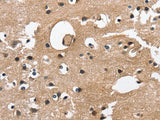

Reactivity Human, Mouse

Applications IHC

Immunogen Recombinant protein of human CAMK1D

Cellular Localization Cytoplasm. Nucleus. Predominantly cytoplasmic (Probable). Also nuclear upon activation.

IHC 1:50-1:200